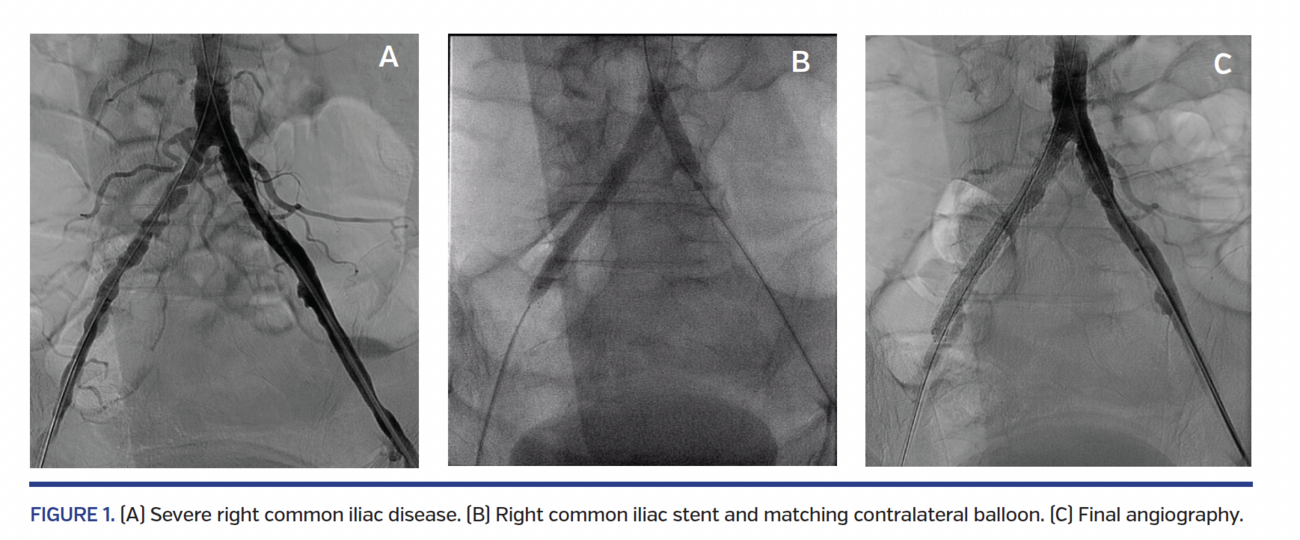

Received wisdom for aortoiliac bifurcation stenting typically dictates the kissing-stent approach using two stents even if critical disease is limited to one side in order not to compromise the contralateral common iliac ostium (CIO). We hypothesized that when critical disease is limited to just one CIO and the contralateral CIO is relatively disease free, one can get away with a single balloon-expandable stent straddling the diseased CIO if the contralateral CIO is protected with a simultaneous matching balloon inflation.

Five patients with a mean age of 65 years were identified; 60% were males, diabetic, and smokers. All patients had disabling unilateral hip and thigh claudication. They underwent stenting of diseased CIO with bare-metal stent while the contralateral CIO was protected with matching balloon inflation. Mean stent diameter and length were 7.8 mm and 46 mm, respectively. Mean matching balloon diameter and length were 7.4 mm and 32 mm, respectively. All target and contralateral CIOs were approached from the ipsilateral common femoral artery (CFA) except one non-diseased CIO, which was approached from the left axillary artery due to severe CFA disease. There were no procedural complications. Non-target CIO remained uncompromised in all cases. All patients went home the next morning and were symptom free at 1 month.

Contrary to received wisdom, predominantly unilateral aortoiliac bifurcation disease can be safely treated with a single stent if the contralateral CIO is protected with matching balloon inflation. Larger studies on this novel approach with a longer clinical follow-up are needed to validate our results.